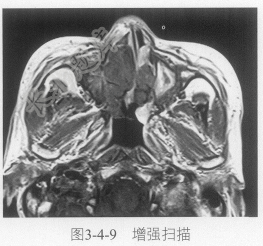

- 单项选择题4.进一步鼻窦MRI平扫及增强扫描见图3-4-7~图3-4-9。肿块信号特点是:

A、软组织肿块T

WI等稍高信号,T2WI为等低信号,增强扫描强化明显B、软组织肿块T

WI等信号,T2WI等信号,增强扫描无明显强化C、肿块多中心多发

D、鼻窦黏膜增厚,提示慢性炎症恶变

E、肿块没有什么特点